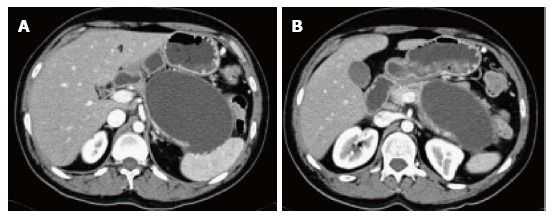

Рисунок 5 | Аксиальные (А, В) КТ-сканы в позднюю артериальную фазу контрастирования и их корональные (С, D) реконструкции.

Тело и хвост поджелудочной железы не накапливают контрастный препарат (полностью замещены некрозом). Гетерогенная область некроза и воспаления перипанкреатической жировой клетчатки. Стрелка указывает на тромбированную селезеночную вену (локальное осложнение процесса).

Рисунок 6 | На аксиальных КТ-сканах в портовенозную фазу поджелудочная железа слегка увеличена и несколько гетерогенно накапливает контрастное вещество.

Вентральнее железы можно увидеть скопление гомогенной жидкости без видимых стенок. Содержимое скопления не накапливает контраст. Эти признаки характерны для острого перипанкреатического скопления жидкости.